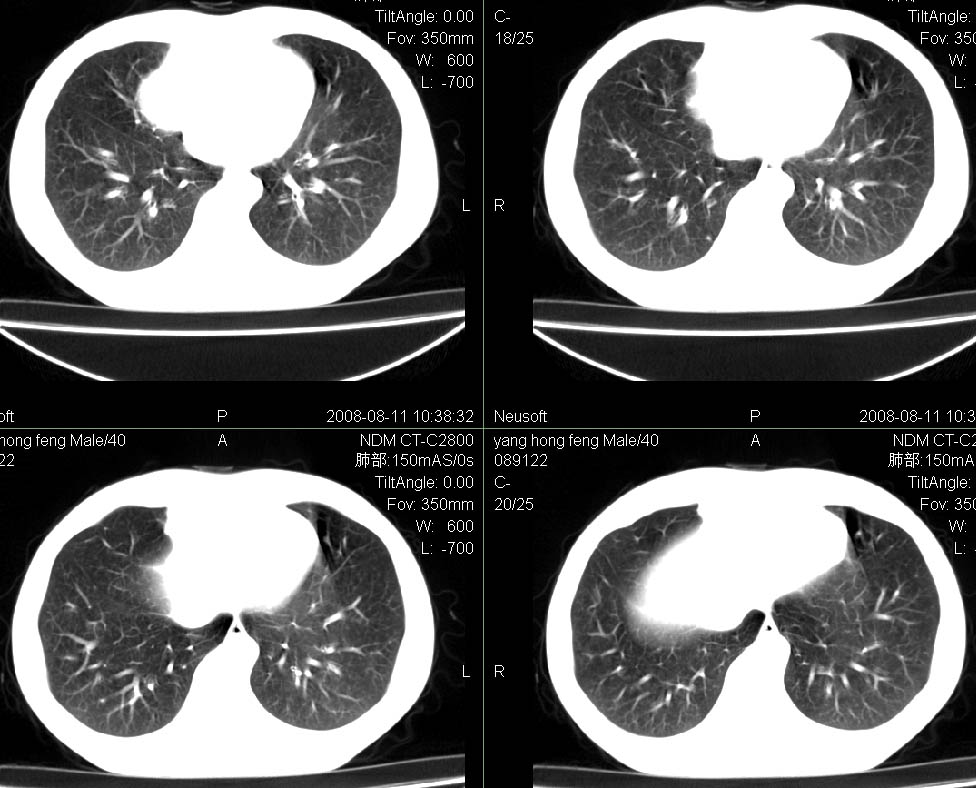

标题: CT15138:男,40,咳嗽胸痛. [打印本页]

标题: CT15138:男,40,咳嗽胸痛.

外院穿刺未见癌细泡,结核菌素实验阳性,未正规治疗2个月复查病灶及纵隔淋巴结增大

右肺中叶肺癌,纵隔淋巴结转移.

考虑   右肺中叶肺癌,纵隔淋巴结转移.建议穿刺活检。炎性假瘤待排

考虑右肺中叶周围型肺癌并纵隔淋巴结转移。